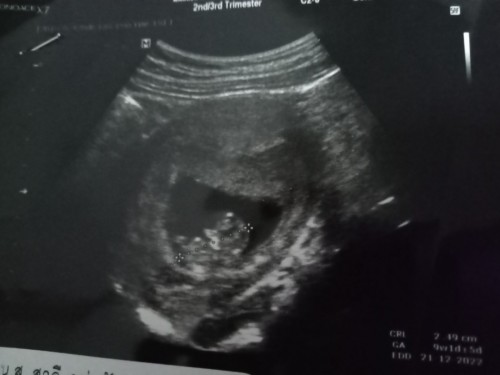

บ้านนี้ ไปซาวตอน 10 w กำหนด 4 มกราคม 66 แพ้หนักมากคะ